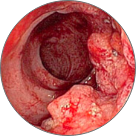

Тромбоза на хемороидалните јазли со локална некроза на ткивото

Венозна стаза во патолошки изменети проширени вени

Крвавење од потслизестите крвни садови, што доведува до некроза на ткивото и анемија

Ректален карцином